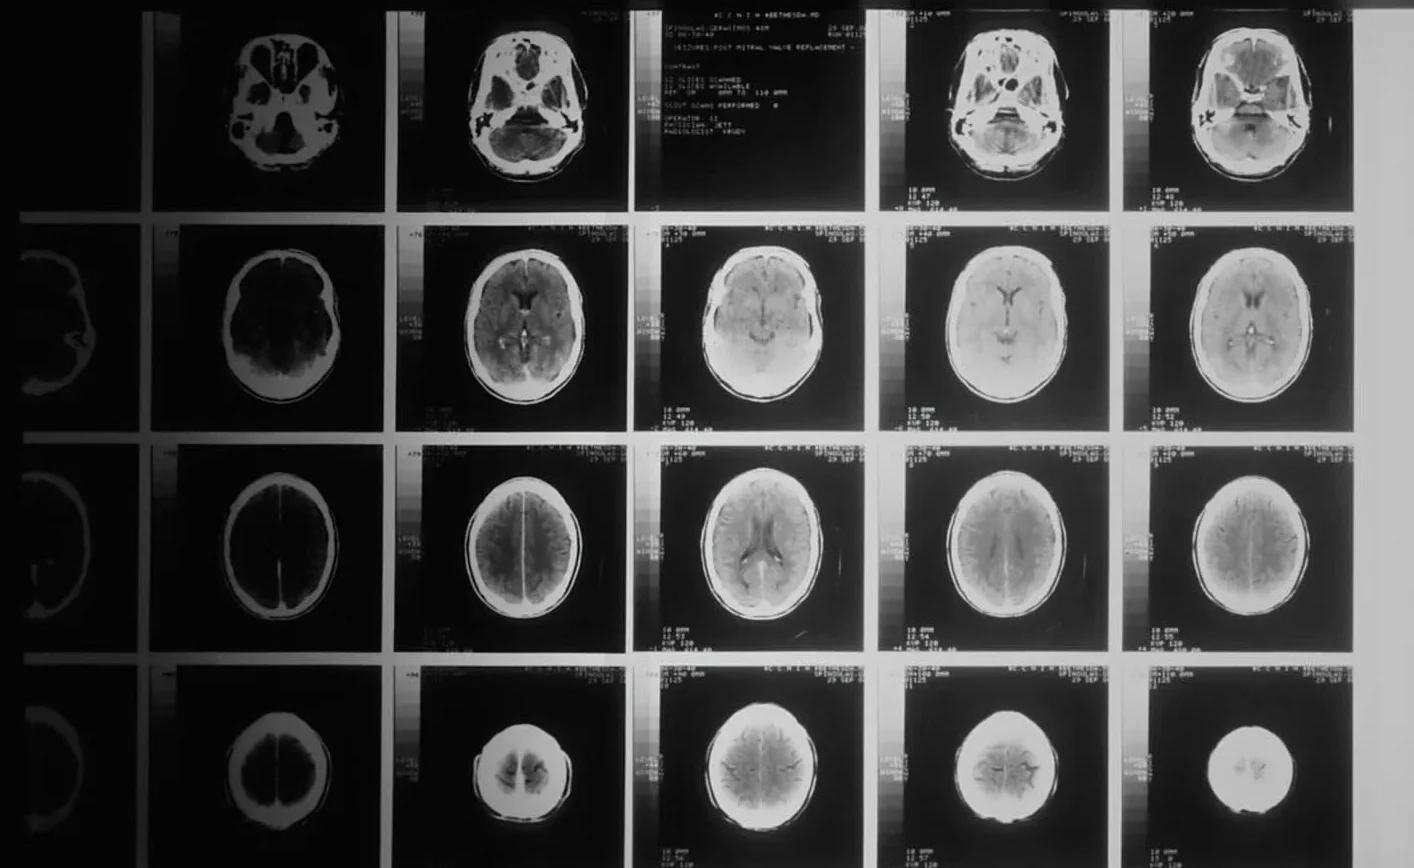

O DIPG é considerado um dos cânceres pediátricos mais letais. Localizado na base do cérebro, afeta funções vitais como respiração, deglutição e equilíbrio. A média de sobrevivência após o diagnóstico é de apenas nove meses.